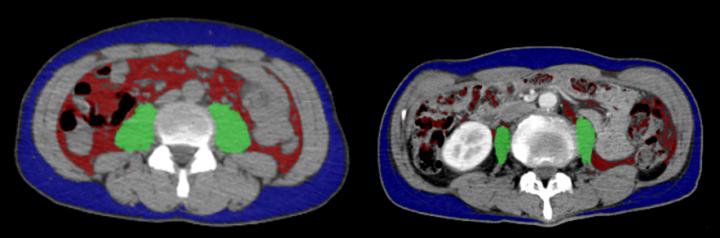

To do this, the researchers examined the medical records and treatment outcomes of 42 patients with advanced NSCLC who were treated with PD-1 inhibitors. Only patients who had undergone an assessment of skeletal muscle mass prior to treatment were included in the analysis.

In fact, while 38.1% of non-sarcopenia patients remained in remission 1 year after treatment, only 10.1% of sarcopenia patients showed no sign of tumor progression at the same time point. "Our findings suggest that baseline skeletal muscle mass has a substantial impact on PD-1 inhibitor efficacy. As such, skeletal muscle mass might be useful for predicting whether treatment is likely to be effective." says Shiroyama.